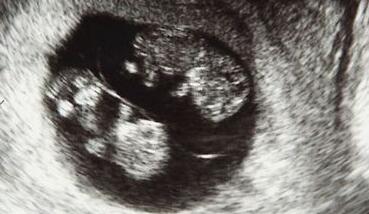

錯位與妊娠周數有很大的關係。一般如果在30周前發現胎兒的位置是不正確的,只要加強觀察就可以了,在此期間,寶寶的個體、活動空間較大,胎位不固定,大概在32周后,胎兒的位置基本固定,所以準確的母親在妊娠30周內糾正胎位時間最好32周。